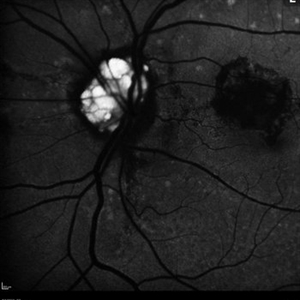

Wyburn Mason Racemose Angiomatosis

Color fundus montage of an 13-year-old female with arteriovenous malformation (Wyburn Mason Racemose Angiomatosis) affecting her right eye. The retinal arteriovenous malformation appears to be stable. She presented with NLP in the eye, strabismus, and peripheral retinal ischemia. She is at risk for neovascular complications; however, she is currently being treated with Sirolimus. Since she is on this systemically, there is no need to perform intraocular anti-VEGF injections or PRP laser. She also presented with optic atrophy affecting her left eye, secondary to chiasmal involvement of arteriovenous malformation. She has had a potential progressive visual field loss involving the temporal aspect of her visual field from the left eye. There is sector optic atrophy. Presumably, this is due to a compressive effect of her arteriovenous malformation on the nasal nerve fiber layer (corresponding to the temporal visual field) crossing to the right occipital cortex at the chiasm.

Photographer: Olivia Rainey

Imaging device: Topcon 50dx

Condition/keywords: arteriovenous malformation, color fundus photograph, color photo, montage, peripheral ischemia, Sirolimus